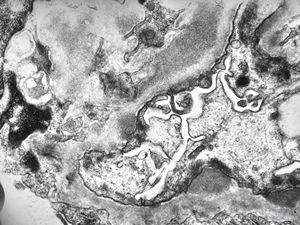

M,17y. | Alport syndrome - split and laminated basement membranes

F,14y. | Alport syndrome - split and laminated, thick/thin basement membranes